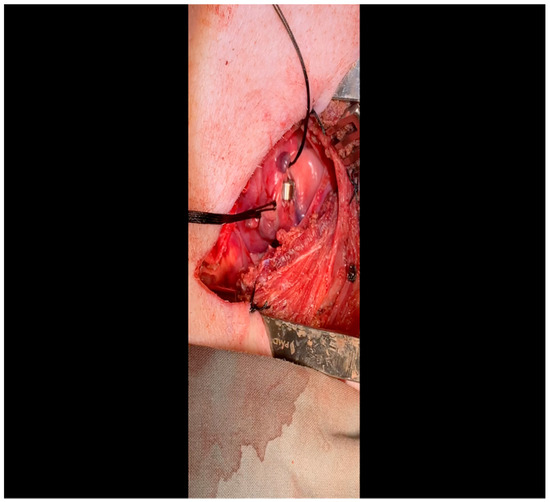

- The pericardium is opened (Figure 3) with scissors. It is important to identify and protect the phrenic nerve.